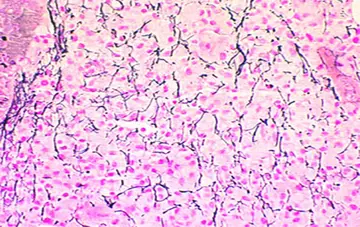

هماتولوژی - صفحه 6